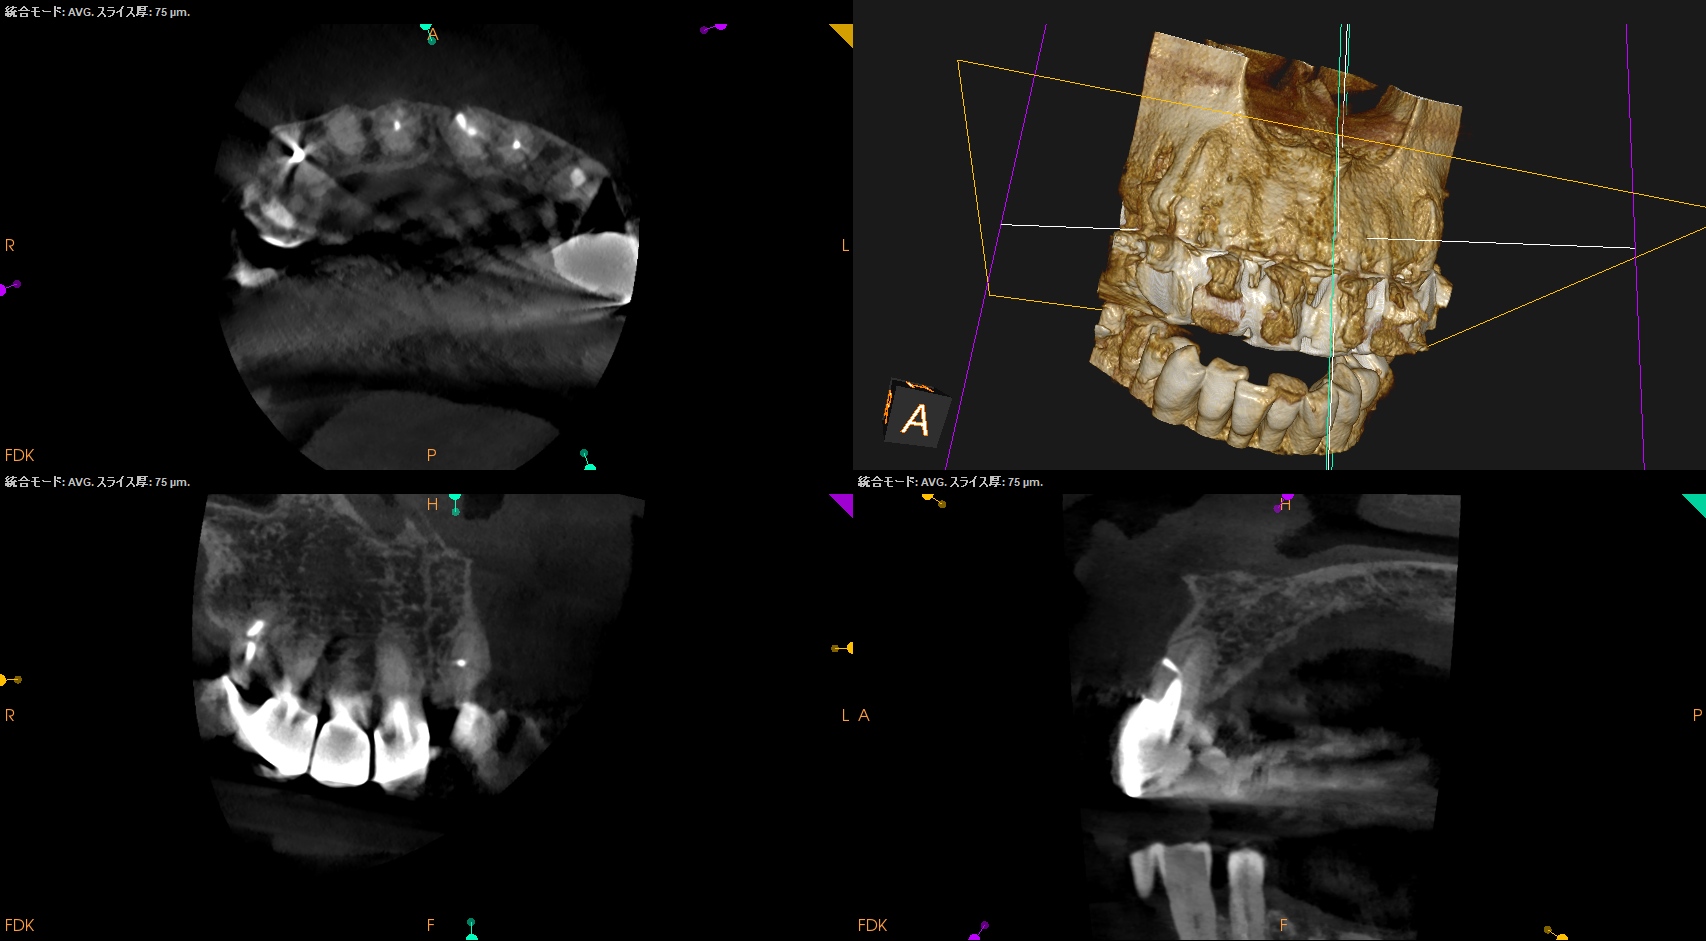

#8,9 Microsurgery 1yr recall(2026.3.11)

#8

#9

#8,9(B)

初診時と比較した。

問題は大きく解決されている。

初診時のSinus tract, 臨床症状は消失した。

ということでこの2歯をこれ以上経過を見ていく必要はないだろう。